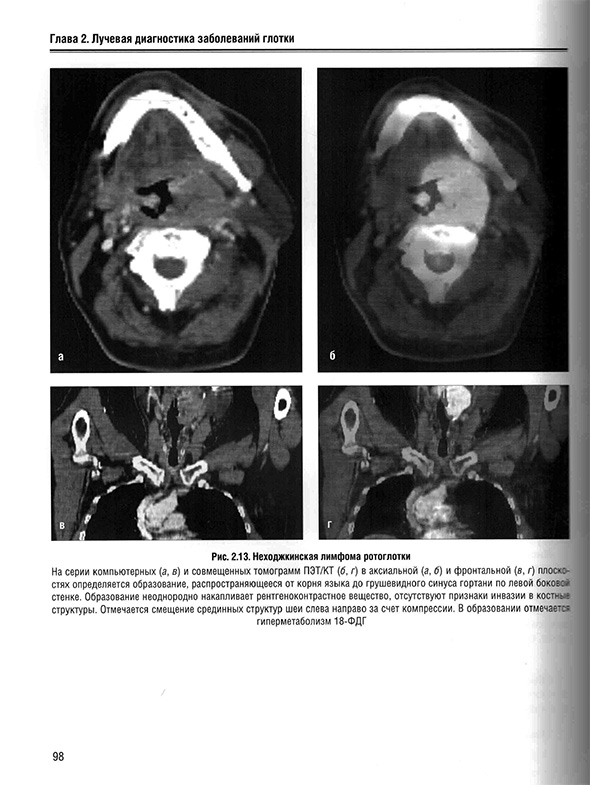

2.7. Неходжкинская лимфома миндалин